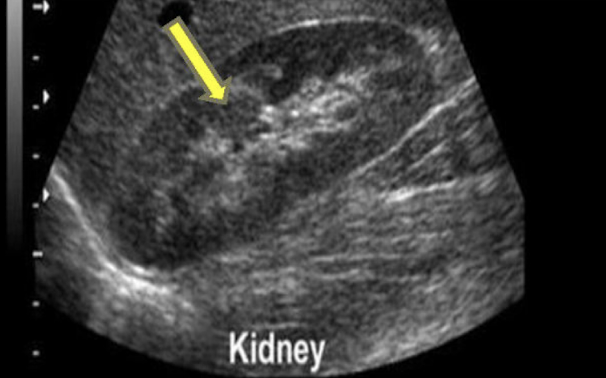

What does CB stand for in this image?

Column of Bertin

Prominent Columns of Bertin can be mistaken for:

a renal mass